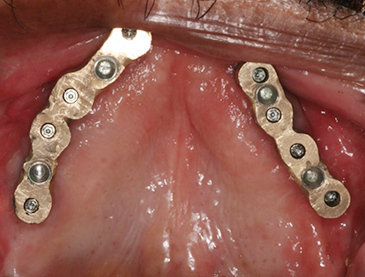

Fully edentulous clinical cases